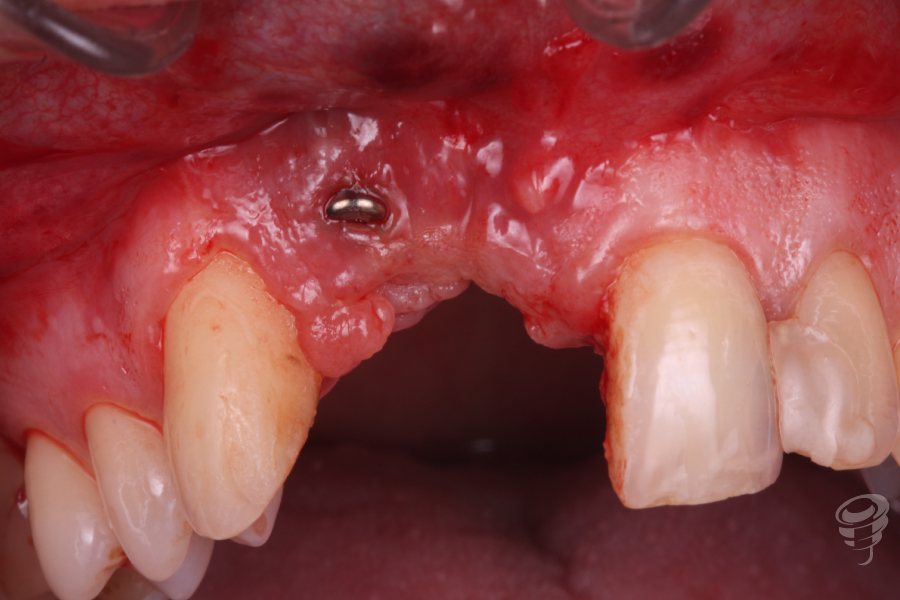

Acude a consulta demandando una solución para un implante situado en posición 12. Este implante nunca se ha rehabilitado debido a su mala situación clínica y radiográfica.

Realizamos un estudio con un CBCT de la zona. En los cortes seccionales se visualiza el implante en una posición muy vestibular, fuera del marco óseo y una imagen radiolúcida rodeando el implante.

Imagen 2